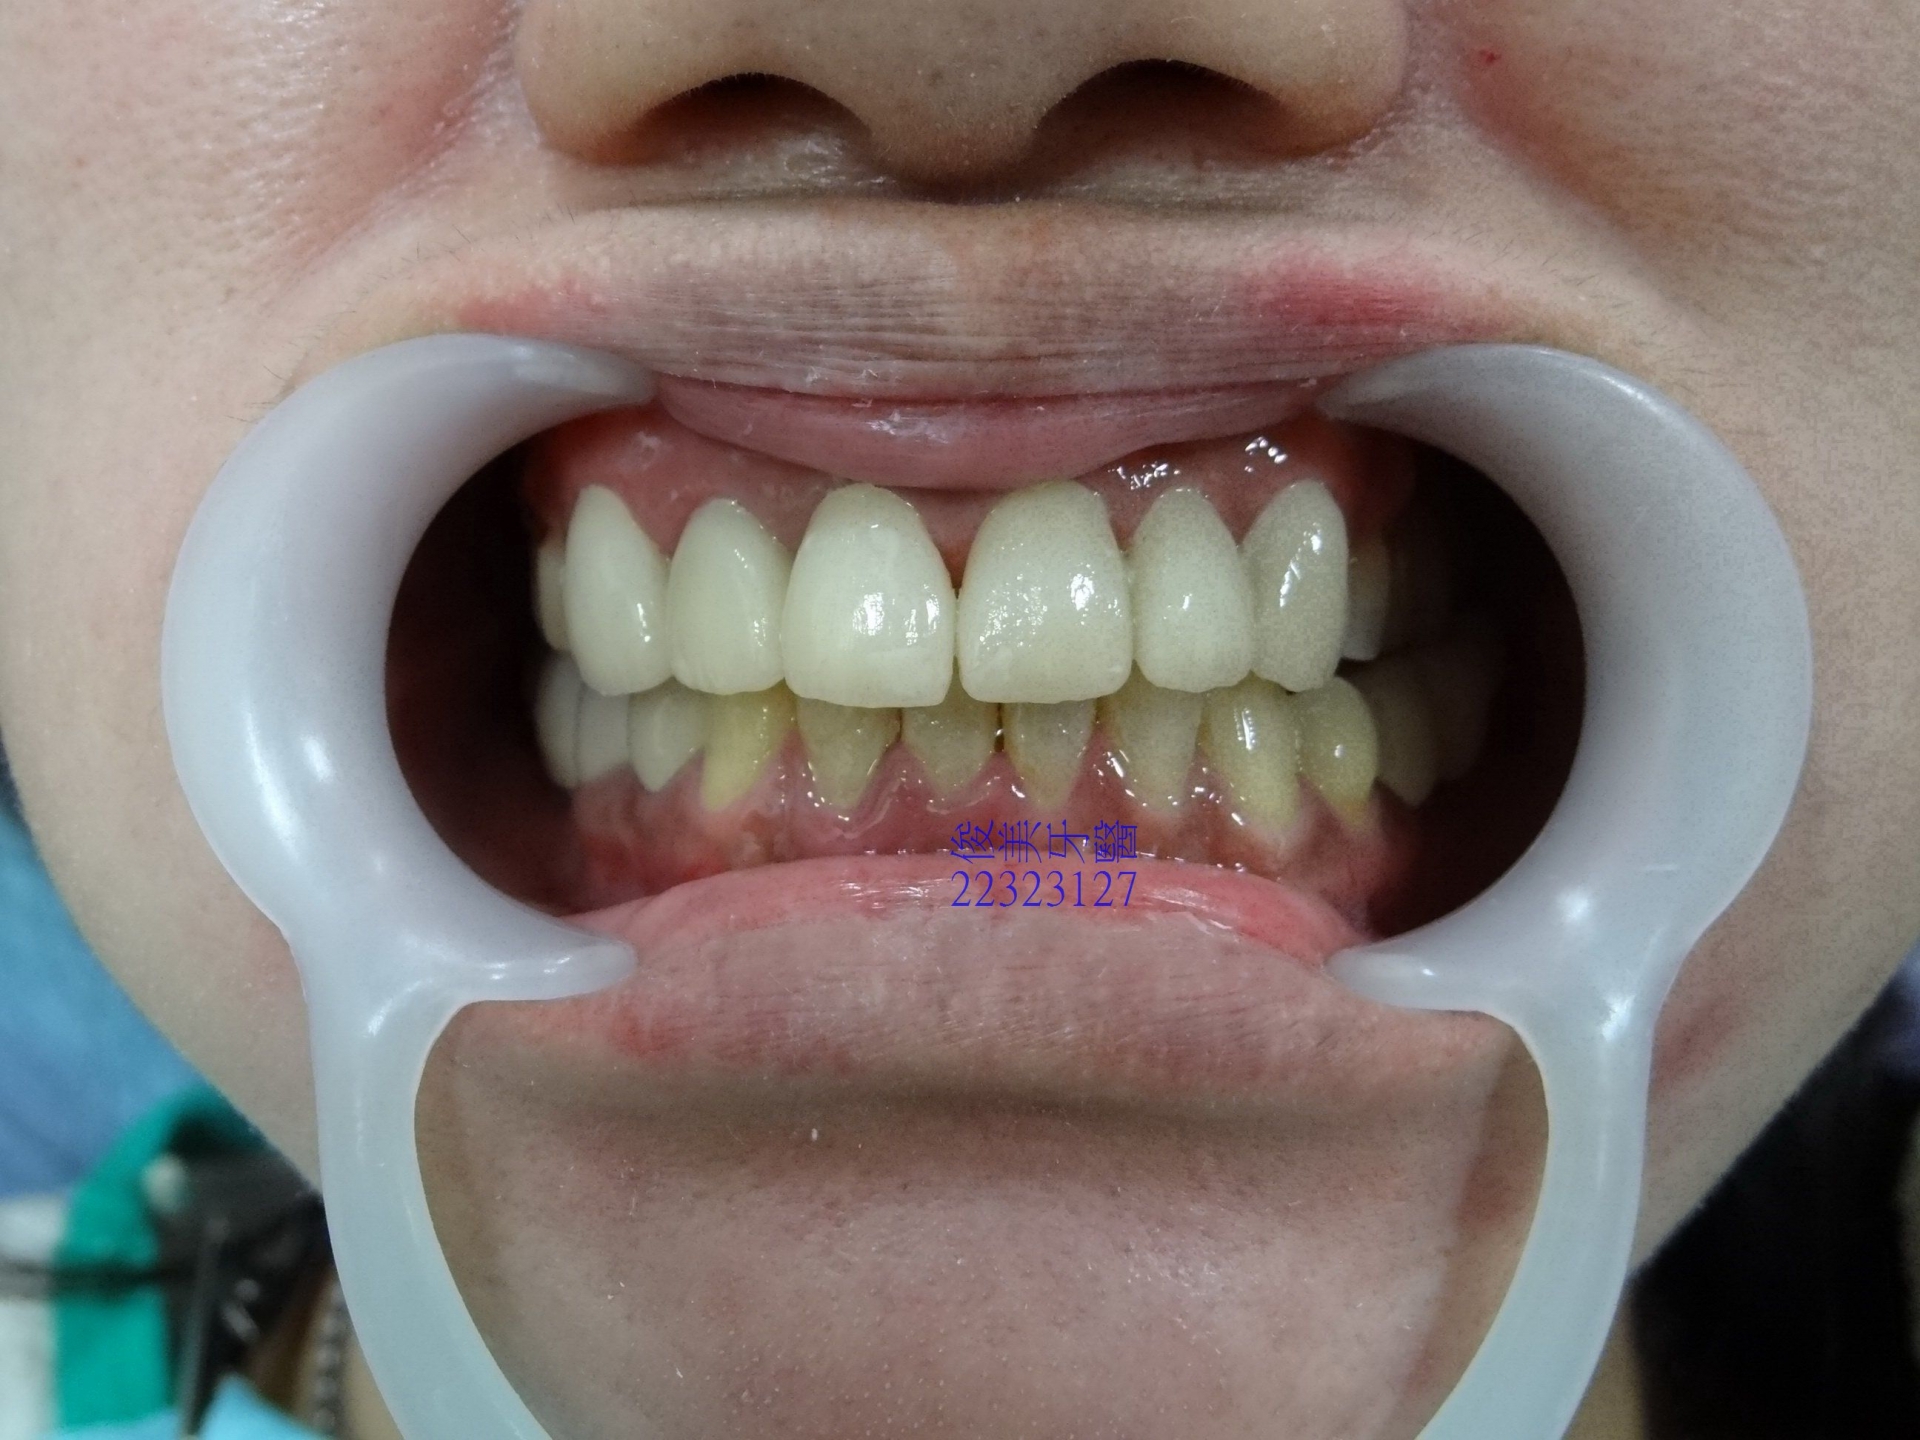

患者原始狀況,反咬,局部牙齦容易出血。

上排牙齒明顯被下排牙侷限住了。

牙齒移位導致牙縫易塞、紅腫。